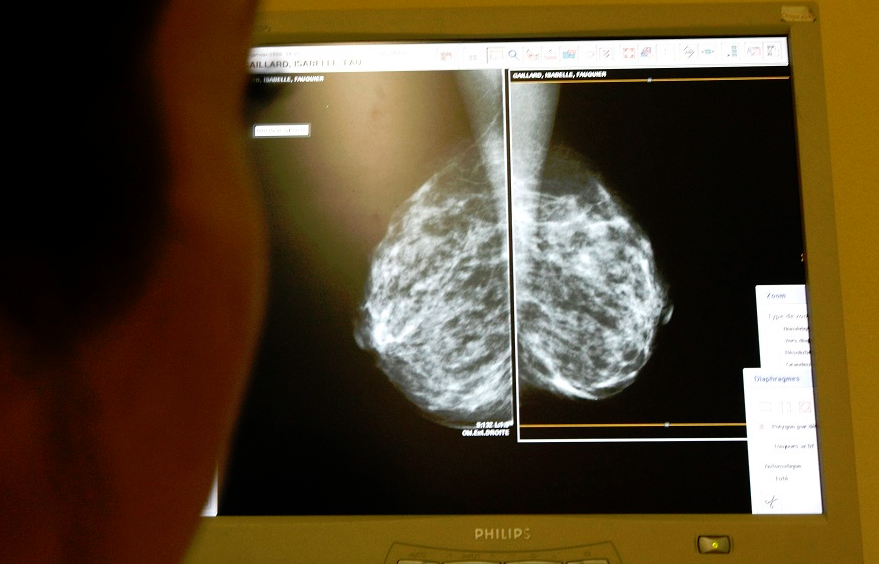

ارتفعت تدريجاً أرقام الإصابة بالسرطان في لبنان وهي أعلى بقليل من تلك التي تسجل في المنطقة (رويترز) صحة لبنان في المرتبة الأولى بإصابات السرطان… فهل التشكيك بالأرقام مبرر؟ by admin 9 أكتوبر، 2025 written by admin 9 أكتوبر، 2025 119 كشفت دراسة جديدة عن نسب مقلقة في معدلات انتشاره والوفيات الناتجة من هذا الداء ما أثار جدلاً واسعاً بين داعين إلى التحرك لمواجهة مخاطره ومن لا يثقون كثيراً بنتائجها اندبندنت عربية / كارين اليان ضاهر صحافية لبنانية @eliane_carine في الأعوام الأخيرة، يلاحظ ارتفاع واضح في معدلات الإصابة بالسرطان في العالم، وفي لبنان بصورة خاصة. إنما في لبنان، يظهر الواقع على الأرض ارتفاعاً في هذه المعدلات في ظل غياب الأرقام التي تؤكد هذا الانطباع، إذ لا تتوافر أي إحصاءات يمكن أن تؤكد هذا الواقع، وتعكس حقيقة المشهد، فكل ما يحكى في هذا المجال لا يستند إلا إلى تقديرات. إلا أن ما كشفته دراسة جديدة نشرت في مجلة “لانسيت” العلمية أحدث جدلاً واسعاً في البلاد، إذ توقعت بأن يتصدر لبنان معدل الوفيات الناتجة من السرطان على مستوى العالم بنسبة تقدر بقرابة 80 في المئة بحلول عام 2050، وقدمت الدراسة أرقاماً مقلقة حول مرض السرطان في بلدان عديدة، واحتل لبنان المرتبة الأولى من حيث عدد الوفيات الناتجة من هذا الداء، مما أثار جدلاً واسعاً وتشكيكاً حتى من قبل البعض حول مدى صحة هذه الأرقام، وإن كانت معدلات الإصابة بالسرطان في لبنان تبدو فعلاً مرتفعة في الظاهر. أرقام مقلقة والواقع مجهول في الدراسة التي نشرت في مجلة “لانسيت” العلمية، قدم أكثر من 2000 باحث تقريراً سنوياً حول بيانات السرطان العالمية، ونشر التقييم ضمن برنامج Global Burden Of Disease فبدا مثيراً للقلق من حيث الأرقام المطروحة في ما أظهره من أعباء هائلة للمرض. وتبين أن عدد الإصابات الجديدة بالسرطان قد تضاعف بمعدل يتخطى المرتين بين عامي 1990 و2023 ليبلغ 18.5 مليون مصاب عام 2023. كما ارتفع عدد الوفيات بنسبة 74 في المئة في الفترة نفسها، ليبلغ 10.4 مليون وفاة عام 2023 على رغم التطورات الحاصلة في التشخيص والعلاج. وتوقع التقرير تشخيص 30.5 مليون إصابة بالسرطان، وأن يموت بسببه 18.6 مليون شخص عام 2050 بحيث تبلغ الزيادة 61 في المئة في معدلات الإصابات و75 في المئة بمعدلات الوفيات، واللافت في التقرير أن معدلات الوفيات بالسرطان قد ارتفعت في الدول الغنية بنسبة 33 في المئة خلال 30 عاماً، في وقت ارتفعت بنسبة 14 في المئة بالدول الفقيرة بسبب تراجع جودة الرعاية الطبية، ومن المتوقع أن يحصل أكثر من نصف الإصابات الجديدة وثلثا الوفيات الجديدة في الدول المنخفضة والمتوسطة الدخل. سرطان الثدي في أعلى المراتب بين مختلف أنواع السرطان في لبنان (رويترز) أما في لبنان، فيظهر التقرير أنه سجل أعلى ارتفاع في معدلات الوفيات بالسرطان فارتفعت من 65,2 إلى 117,3 وفاة لكل 100 ألف نسمة بين عامي 1990 و2023. في المقابل، سجل أعلى معدل انخفاض في معدل الإصابات في الإمارات العربية المتحدة، فانخفض بمعدل النصف من 243 إلى 102,9 لكل 100 ألف نسمة. وتعد فرنسا من الدول الـ10 الأولى من حيث معدلات الإصابة بالسرطان بالنسبة إلى عدد السكان، لكن تراجعت الوفيات فيها من 184,7 إلى 136,8 وفاة لكل 100 ألف نسمة بين عامي 1990 و2023. وتعد غرينلاند ومنغوليا وأوروغواي من الدول التي تسجل فيها أعلى نسبة وفيات بالسرطان. رداً على هذه الدراسة، أصدر وزير الصحة العامة اللبناني ركان ناصر الدين بياناً جاء فيه أن “البيانات الواردة في المقال تستند إلى افتراضات ونماذج معدة سابقاً وليس إلى أرقام واقعية متاحة، إذ إنه حتى الآن لا توجد في لبنان بيانات علمية دقيقة حول الوفيات الناجمة عن مرض السرطان. وقد تكون توقعات The Lancet مبالغاً بها أو غير دقيقة بصورة مطلقة. على رغم ذلك، فإن البيانات الواردة في المقال تشكل ناقوس خطر لجميع المعنيين بالسياسات الصحية في لبنان من أجل العمل على وضع حد للزيادة المتوقعة في الوفيات الناجمة عن مرض السرطان، علماً أن وزارة الصحة تعمل على مراجعة المادة المطروحة في المقال وتحليلها”. أضاف البيان “الجميع يدركون الارتفاع في معدلات التدخين بلبنان، في ظل غياب كلي لأدنى إجراءات الرقابة الهادفة لتخفيض معدلات التدخين الخطرة والمتسببة بالأمراض، كما أنه ليس خفياً على أحد ارتفاع نسب التلوث التي يعانيها لبنان لأسباب شتى وغير ذلك من أنماط غير صحية ومتسببة بالأمراض. إن الخطة الوطنية لمكافحة السرطان التي وضعتها وزارة الصحة العامة تهدف إلى إيجاد الحلول لهذه المشكلات الأساسية التي نعانيها في لبنان، لكن التوصل إلى النتيجة المتوخاة يتطلب تعاوناً فعلياً من جميع المعنيين على أساس إدراك حجم الأخطار الصحية التي يواجهها اللبنانيون. بناء عليه إننا نحث واضعي السياسات على التعاون مع الوزارة لعدم التلكؤ وإيجاد تبريرات تحول دون المضي قدماً في سبل تحسين أنماط الحياة الصحية في لبنان، والعمل على إقرار الإجراءات الضرورية والصارمة والتشدد في تطبيقها بهدف الحد من عوامل الخطر المتسببة بمرض السرطان في لبنان وتخفيض نسبة الإصابة بهذا المرض”. ثغرة أساسية في رده على ما ورد في الدراسة، أوضح طبيب أمراض الدم والأورام في المركز الطبي للجامعة الأميركية في بيروت البروفيسور عرفات طفيلي أن الدراسة تعطي نظرة عامة عن عدد حالات السرطان، إلا أن الثغرة الأساسية التي فيها أنها لا تستند إلى الأرقام الفعلية، بل إلى تقديرات وتوقعات. وإذ لا يعني ذلك أن الدراسة ليست علمية، إلا أن مجال الخطأ يزيد مع زيادة التقديرات. وكانت قد سبقت هذه الدراسة دراسة مماثلة عام 2018 أتى في نتائجها أنه، عام 2022، ستسجل 20 ألف حالة سرطان، فيما أظهر الواقع أنه في لبنان اليوم 12 إلى 13 ألف إصابة سرطان عام 2022، بحسب الأرقام الأخيرة. فعام 2022، أظهرت الأرقام أن معدلات الإصابة بالسرطان بلغت 13390 إصابة. هذا ما يؤكد أن الدراسة التي تبنى على التقديرات، يكون مجال الخطأ فيها كبيراً”. من جهة أخرى أشار طفيلي إلى أنه في الغرب هناك معدلات وفيات مرتفعة جداً، والأرقام في لبنان ليست استثنائية، لكن حتى الآن ليست هناك أرقام حول معدلات الوفيات في لبنان بسبب السرطان، في وقت صدرت عام 2024 الأرقام التي تظهر معدلات الإصابة بالمرض بعد أعوام من غياب أي أرقام فعلية وإحصاءات من عام 2016، مضيفاً أيضاً “لا يمكن أن ننكر أن الأرقام تظهر ارتفاعاً تدريجاً في معدلات الإصابة بالسرطان، لكنها إلى حد ما ثابتة في الأعوام الأخيرة ولا تظهر ارتفاعاً خيالياً كما يتصور البعض، لكن في ما يتعلق بالوفيات، فإن جمع الأرقام الخاصة بها يتطلب أعواماً عديدة من المتابعة للمرضى ونسب الوفيات بينهم”. وأجرت الدراسة مقارنة بين أرقام السرطان في لبنان ودول أخرى عديدة هي في معظمها من دول العالم الثالث. هذه المقارنة، بذاتها، لا تعد منطقية بحسب طفيلي، وإن كان ذلك لا يعني أن الباحثين ليسوا علميين. وصحيح أنه في لبنان تسجل معدلات سرطان أعلى بقليل من تلك التي في دول المنطقة، لكن تلك الأرقام هي أعلى بعد في دول الغرب، ولا بد من النظر في ذلك إلى معدلات التشخيص والكشف التي قد تكون مرتفعة، وتسهم في ارتفاع الأرقام. يضاف إلى ذلك أن النظام الصحي يعد متطوراً في لبنان، وترتفع معدلات التشخيص وكشف السرطان فيه. في الوقت نفسه لا يمكن إلا النظر إلى هذه الدراسة لاعتبارها بمثابة ناقوس خطر، خصوصاً أن الواقع يظهر عوامل عديدة تسهم في ارتفاع مقلق متوقع في معدلات الإصابة بالسرطان في الأعوام المقبلة. فيكفي أن معدلات التدخين بأنواعه مخيفة، وهي تطاول الفئات العمرية كافة ولا تتوافر أي سياسات لمكافحة هذه الآفة، لا بل على العكس ثمة جهود لحماية قطاع التدخين والسياحة بعدم وضع سياسات لمنع التدخين. معدلات التدخين في لبنان الأعلى في العالم بحسب طفيلي أيضاً، “قد تكون معدلات التدخين في لبنان الأعلى في العالم، وهذا ما ينذر باحتمال تسجيل معدلات مقلقة من السرطان في السنوات المقبلة، إذا ما استمر الوضع على حاله. فالمطلوب حالياً العمل على مكافحة عوامل الخطر التي يمكن التحكم بها لتغيير الأرقام ومواجهة الخطر بفاعلية، وأبرزها السمنة والتدخين”. أما أعلى معدلات سرطان في لبنان فهي حالياً سرطان الثدي بين النساء، وسرطانات الرئة والبروستات لدى الرجل. وفي ما يتعلق بسرطان الرئة، لا يزال يشخص في مراحل متأخرة بنسبة 70 في المئة من الحالات، كما في باقي الدول إذ تعد معدلات التشخيص المتأخر فيه مرتفعة. في المقابل، يحقق لبنان مراتب متقدمة بتشخيص سرطان الثدي في مراحل مبكرة، إضافة إلى توافر علاجات جيدة ومتطورة في البلاد. وكان تقرير، “منظمة الصحة العالمية” لعام 2022 قد كشف عن أن سرطان الثدي يحتل المرتبة الأولى بين أكثر السرطانات انتشاراً في لبنان إذ يشكل نسبة 16,6 في المئة من الإصابة، ليأتي بعده في المرتبة الثاني سرطان الرئة بنسبة 12 في المئة، ثم سرطان البروستات بنسبة 8,3 في المئة، وسرطان القولون بنسبة 7,7 في المئة، وسرطان المثانة بنسبة 5,4 في المئة، واللمفوما اللاهودجكينية نسبة 4,9 في المئة من الإصابات، في وقت تجتمع باقي أنواع السرطان لتشكل نسبة 45,1 في المئة. المزيد عن: إصابات السرطانمجلة لانسيتركان ناصر الدينسرطان الثديسرطان الرئةسرطان البروستاتلمفوما لاهودجكينية 0 comment 0 FacebookTwitterPinterestEmail admin previous post ما الذي نعرفه عن المرحلة الأولى من اتفاق غزة؟ next post “ميكانيكا الكم” تفاجئ روادها بـ”نوبل الفيزياء” You may also like اختراق طبي: الذكاء الاصطناعي يكشف ألزهايمر بدقة غير... 11 مارس، 2026 طرق بسيطة لتخفيف أعراض التهاب المفاصل 11 مارس، 2026 سرطان الرئة الأكثر فتكا… والكشف المبكر ينقذ الآلاف 7 مارس، 2026 فتيات يقعن في فخ PPD مع موسم الحناء... 7 مارس، 2026 مفاجأة علاجية… عقار قديم يُظهِر فائدة جديدة للذاكرة 5 مارس، 2026 مسنون يقاومون الخرف: ما سر ذاكرتهم الخارقة؟ 4 مارس، 2026 تغييرات طفيفة في نمط الحياة تقلل من خطر... 26 فبراير، 2026 مارسه صباحاً ومساءً… نشاط يومي قد يبطئ السرطان 24 فبراير، 2026 (7 تغيرات) في الشخصية في منتصف العمر قد... 24 فبراير، 2026 التأمل مرتين يومياً قد يحدّ من تطور السرطان... 24 فبراير، 2026